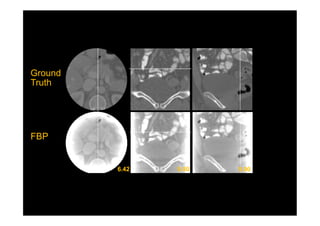

Deep Learning Interior Tomography

Han et al, arXiv preprint arXiv:1712.10248, (2017): CT meeting 2018.

Ground

Truth

FBP

TV

Chord

Line

Ours

8~10 dB